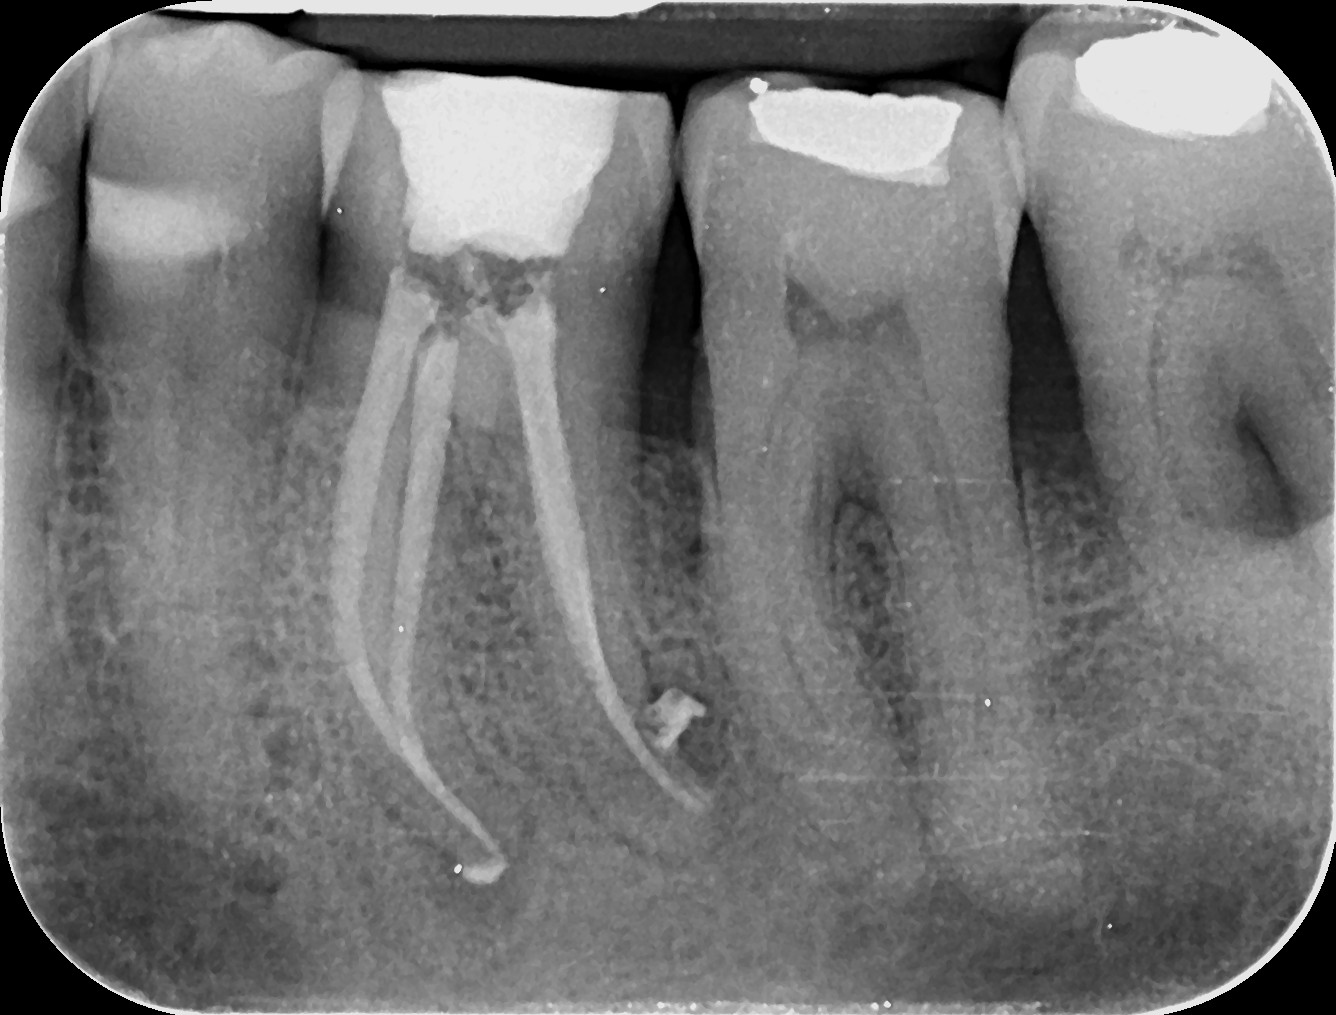

Pacienții necesită un tratament endodontic atunci când la nivelul camerei pulpare sau a canalului radicular există inflamație sau infecție, din cauza unei carii profunde, a unei fisuri sau provocată de un traumatism accidental. Poate fi realizat într-o singură ședință sau în mai multe, în funcție de complexitatea cazului.

În timpul tratamentului, medicul endodont curăță, dezinfectează, prepară canalele radiculare și obturează etanș spațiul creat. Dinții cu destrucții coronare masive necesită ranforsare cu pivoți de fibră de sticlă, iar ulterior vor fi șlefuiți și acoperiți cu lucrări protetice ce redau rezistența structurii dentare restante.